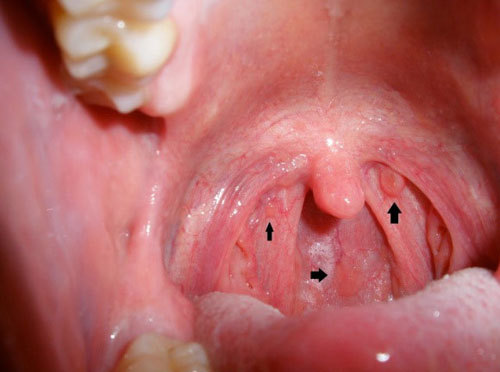

Triệu chứng và dấu hiệu nhận biết bệnh ung thư vòm họng

Khó có thể phát hiện bệnh ung thư này trong giai đoạn đầu. Dấu hiệu và triệu chứng thông thường của ung thư cổ họng bao gồm:

Bề mặt thanh quản thô ráp

Bạn cảm thấy có một bề mặt thô ráp trong cổ họng rất khó chịu? Nếu đã bắt đầu phát triển ung thư vòm họng, bạn sẽ tiếp tục cảm thấy dấu hiệu này.